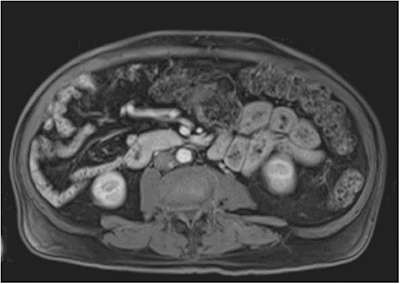

Lab studies revealed an elevated chromogranin A level of 88 and a glucagon level of 1332 mg/dL, diagnostic for glucagonoma. All other NET markers were negative. A magnetic resonance imaging (MRI) study with and without contrast revealed a 5.4 x 3.8 centimeter hyperintense mass (Figure 1) in the uncinate process of the pancreas without evidence of metastatic disease.

Figure 1: MRI showing 5.4 x 3.8 cm hyperintense mass in the uncinate process of the pancreas without evidence of metastatic disease.